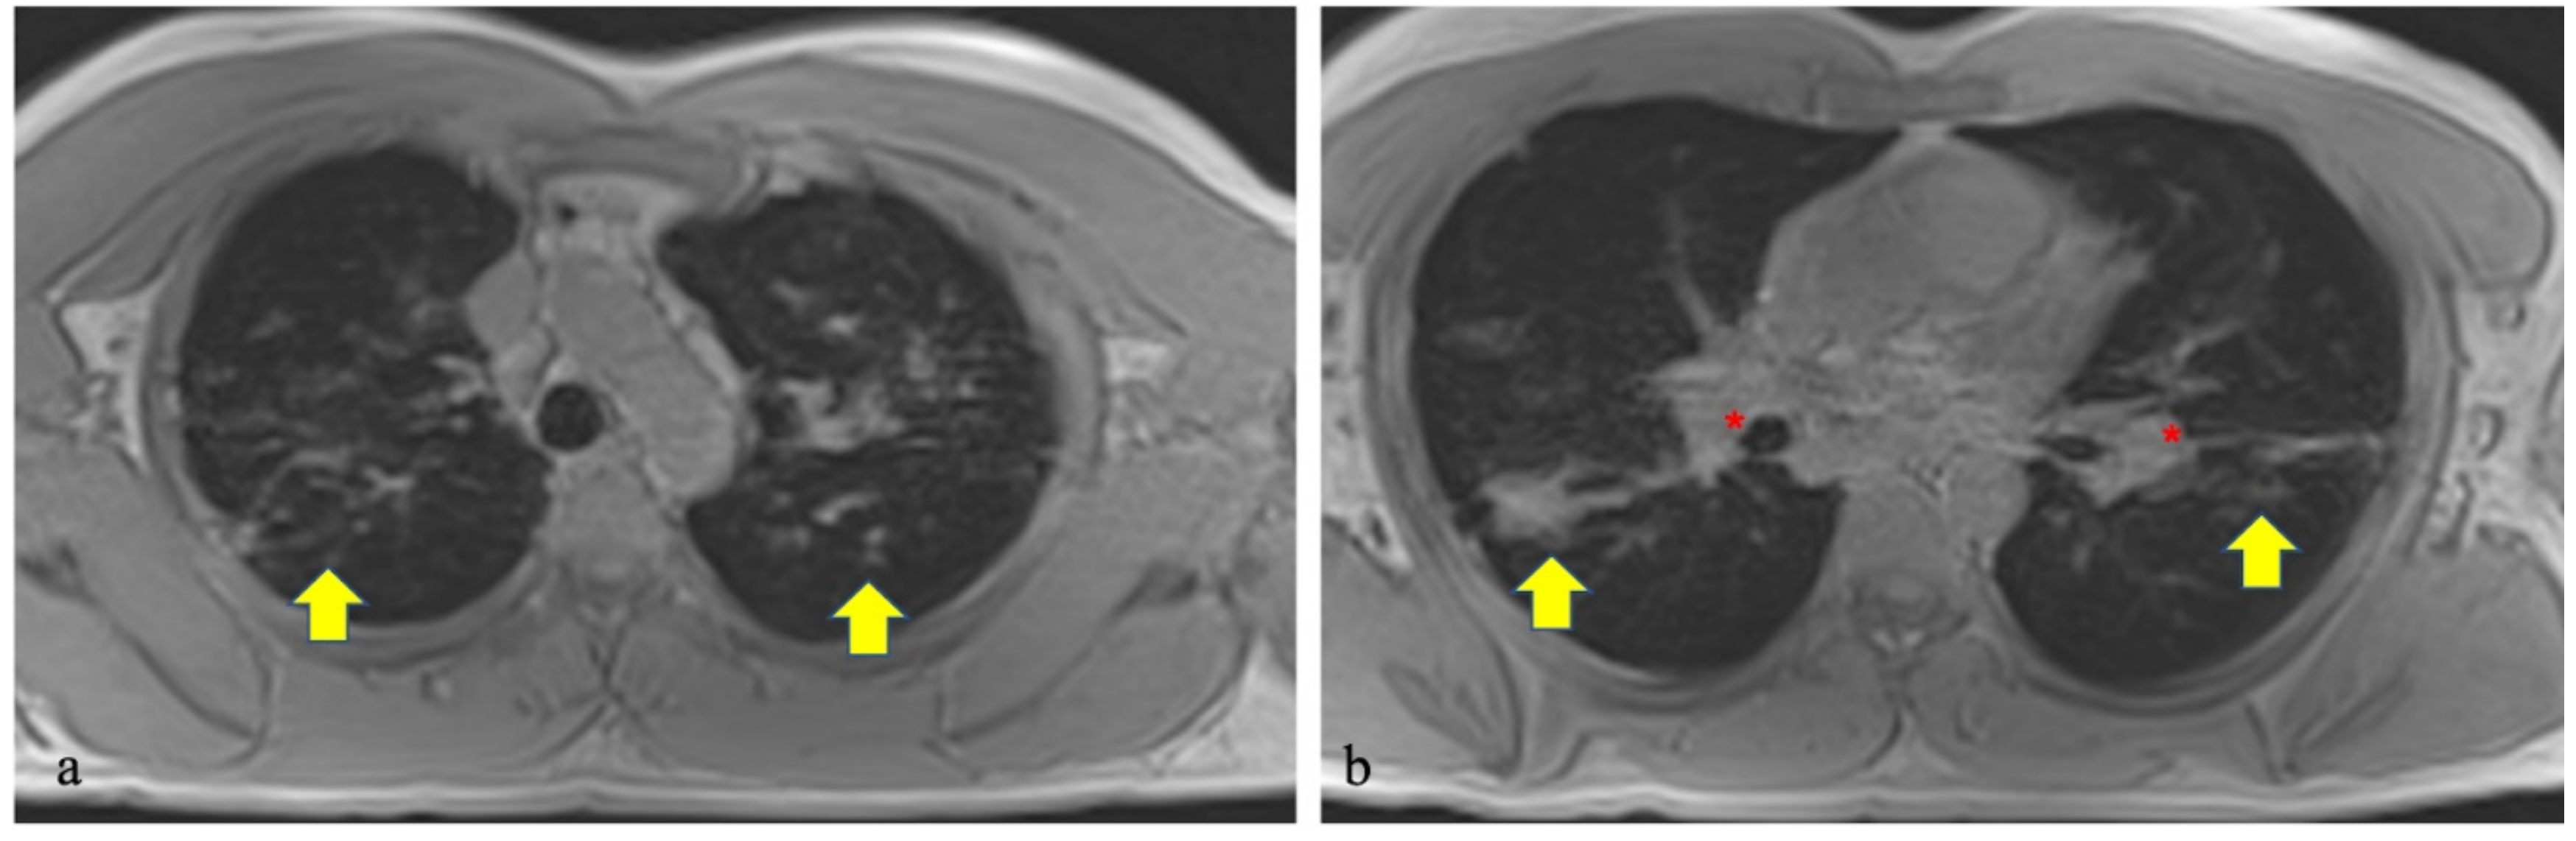

- Ekinci, A.; Yucel Ucarkus, T.; Okur, A.; Ozturk, M.; Dogan, S. MRI of pneumonia in immunocompromised patients: comparison with CT. Diagn. Interv. Radiol. 2017, 23, 22–28. [Google Scholar] [CrossRef]

- Yan, C.; Tan, X.; Wei, Q.; Feng, R.; Li, C.; Wu, Y.; Xu, Y. Lung MRI of invasive fungal infection at 3 Tesla: Evaluation of five different pulse sequences and comparison with multidetector computed tomography (MDCT). Eur. Radiol. 2014, 25, 550–557. [Google Scholar] [CrossRef] [PubMed]

- Yan, C.; Xu, J.; Xiong, W.; Wei, Q.; Feng, R.; Wu, Y.; Xu, Y. Use of intravoxel incoherent motion diffusion-weighted MR imaging for assessment of treatment response to invasive fungal infection in the lung. Eur. Radiol. 2016, 27, 212–221. [Google Scholar] [CrossRef] [PubMed]